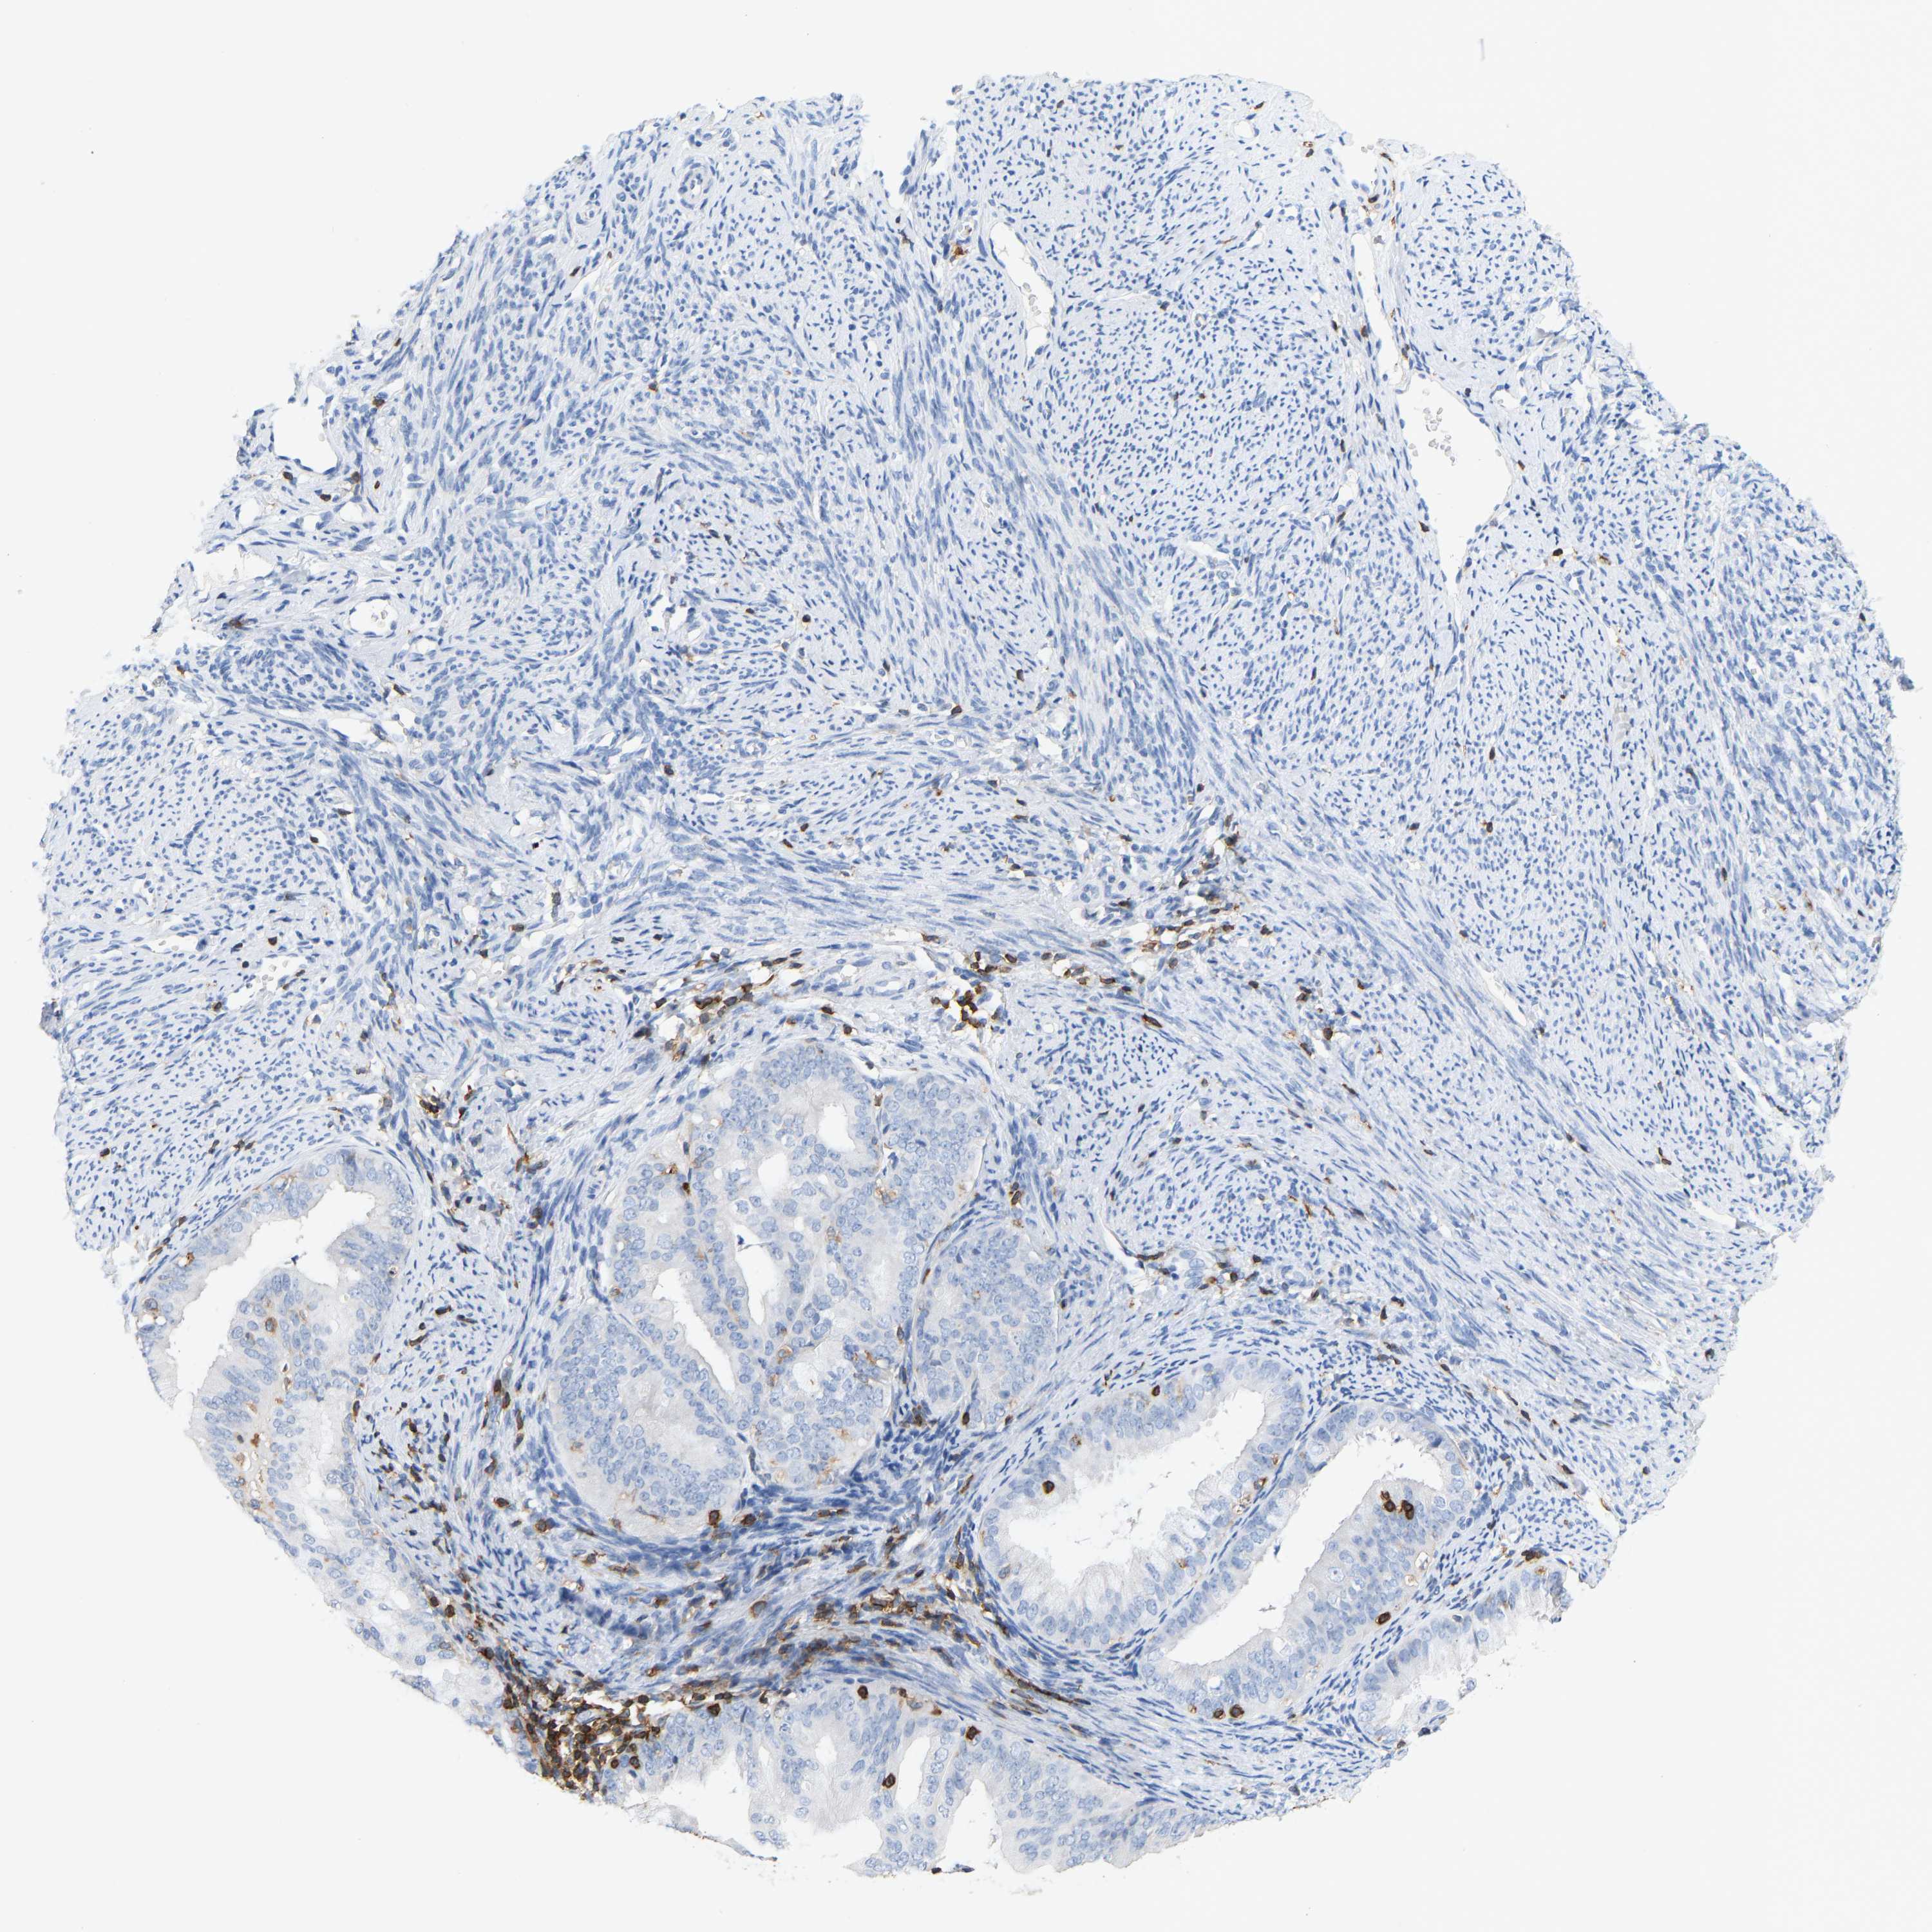

ENDOMETRIAL CANCER - Protein expressioni

A mouse-over function shows sample information and annotation data. Click on an image to view it in a full screen mode. Samples can be filtered based on level of antibody staining by selecting one or several of the following categories: high, medium, low and not detected. The assay and annotation is described here.

Note that samples used for immunohistochemistry by the Human Protein Atlas do not correspond to samples in the TCGA dataset.

Antibody stainingi

Antibody staining in the annotated cell types in the current human tissue is reported as not detected, low, medium, or high, based on conventional immunohistochemistry profiling in selected tissues. This score is based on the combination of the staining intensity and fraction of stained cells.

Each image is clickable and will lead to virtual microscopy that enables deeper exploration of all samples and also displays staining intensity scores, fraction scores and subcellular localization as well as patient and tissue information for each sample.

Antibody HPA018849

Antibody HPA019536

Antibody CAB033987

Staining

High

Medium

Low

Not detected

Intensity

Strong

Moderate

Weak

Negative

Quantity

>75%

75%-25%

<25%

None

Location

Nuclear

Cytoplasmic/membranous

Cytoplasmic/membranous,nuclear